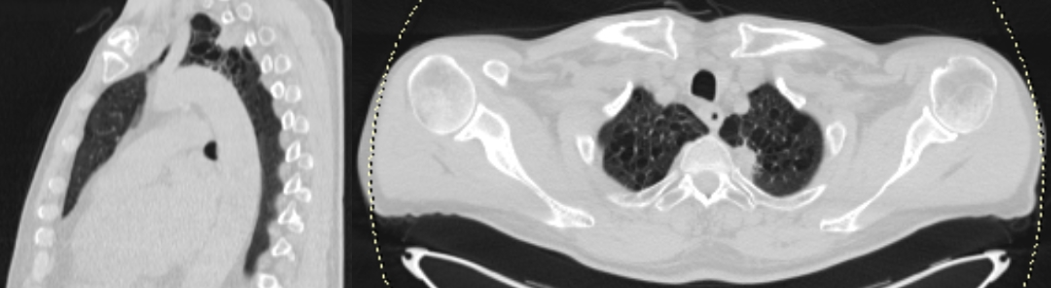

1. Рис. 1. ПЭТ/КТ с 18F-ФДГ (поражение нижней челюсти, шейных лимфатических узлов справа, верхней доли левого легкого при В-клеточной крупноклеточной лимфоме). Примечание: рисунок выполнен авторами | |